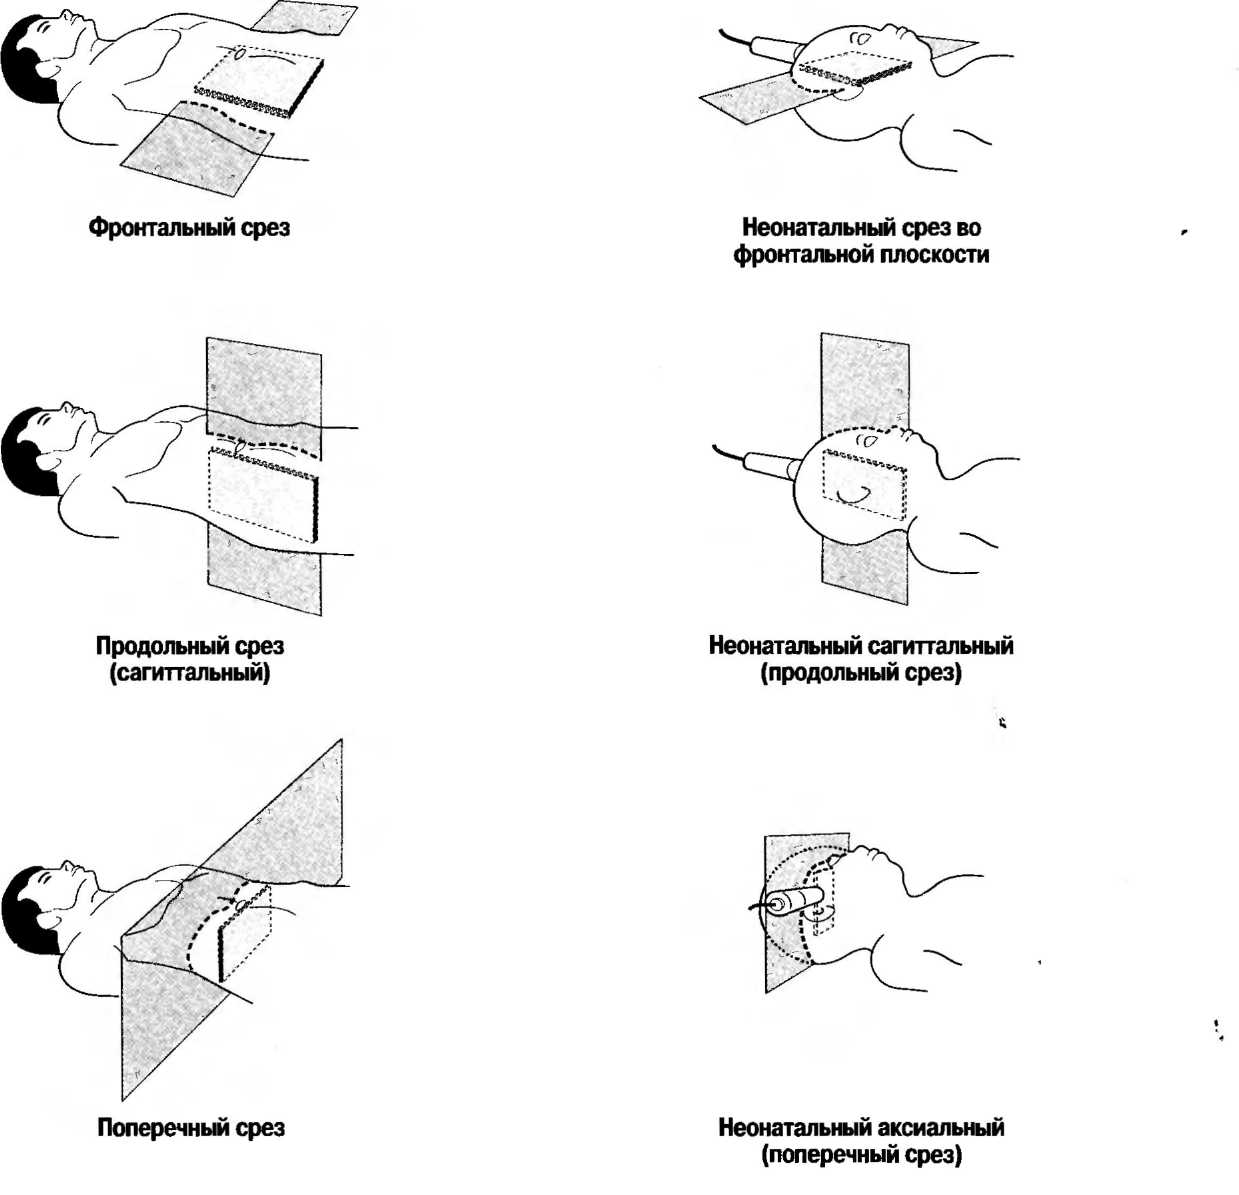

Поперечный срез (аксиальный срез) |

Ультразвуковой срез под прямым углом к длинной оси тела. Термин «аксиальный» обычно используется при обозначении срезов мозга, «поперечный» — при обозначении срезов живота и шеи. Плоскость сканирования может быть перпендикулярной или направленной немного под углом к голове или ногам пациента. Поперечный срез может быть получен в положении пациента на спине, на животе, в положении стоя или на боку. |

Продольный эхографический срез (сагиттальный скан) |

Вертикальный срез по длинной оси тела. Термин «сагиттальный» используется при сканировании в срединной плоскости, особенно при исследовании мозга. Ориентирами, через которые проходит срединная плоскость, являются нос, лобковый симфиз, позвоночник. В случае, если срез не проходит в срединной плоскости, он может называться «парасагиттальным». Термин «продольный» чаще используется при исследовании живота и шеи. Продольный срез также может быть получен в положении пациента на спине, на животе, в вертикальном положении, в положении на боку. |

Срез во фронтальной плоскости |

Плоскость, проходящая через тело по длинной оси (от головы до ног) под прямым углом к срединной плоскости. Чтобы сделать зхографический срез в этой плоскости, необходимо поместить датчик на боковую поверхность тела, направив его к другой боковой поверхности, перемещая его параллельно длинной оси тела. Срез во фронтальной плоскостиможет быть получен в положении пациента на спине, на животе, стоя или лежа на боку. |